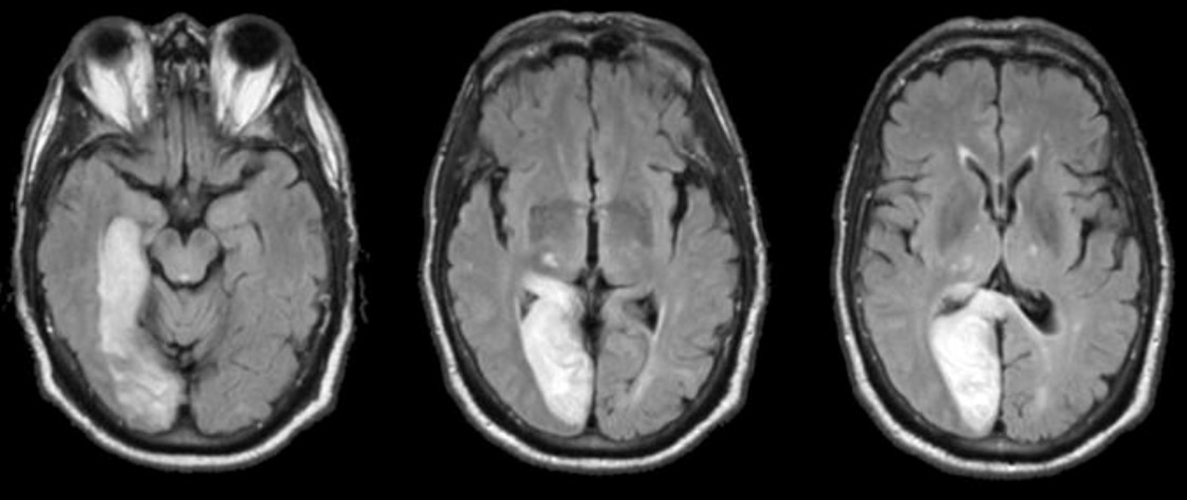

À l’examen clinique : la patiente est désorientée. Elle a une amputation dans les hémichamps visuels gauches des deux yeux. Le testing moteur vous semble légèrement plus faible aux deux membres inférieurs, vous ne parvenez pas à évaluer la sensibilité. Ses réflexes ostéo-tendineux sont vifs aux membres inférieurs, vous retrouvez une extension lente des deux hallux lorsque vous effleurez la plante des pieds avec votre marteau. Lorsque vous regardez les chaussures de la patiente, il vous semble que l’avant de ses chaussures est très abîmé par rapport à l’arrière.